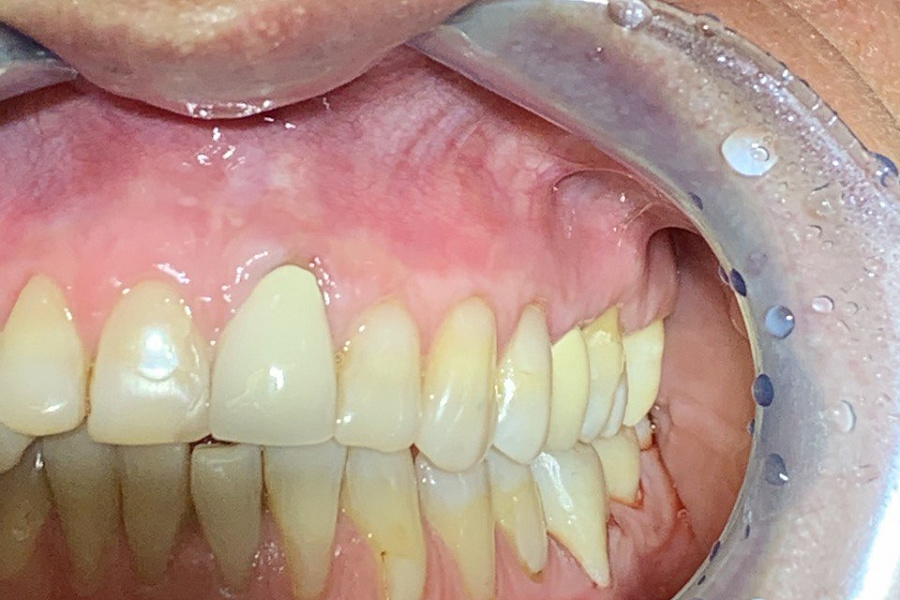

3. Восстановление формы коронок зубов керамическими винирами, чтобы устранить восстановление цвета и формы коронок зубов, убрать окклюзионную травму, восстановить гармоничное движение в височно-нижнечелюстном суставе. Реставрацию проводила доктор Марина Мискевич.

Результат лечения